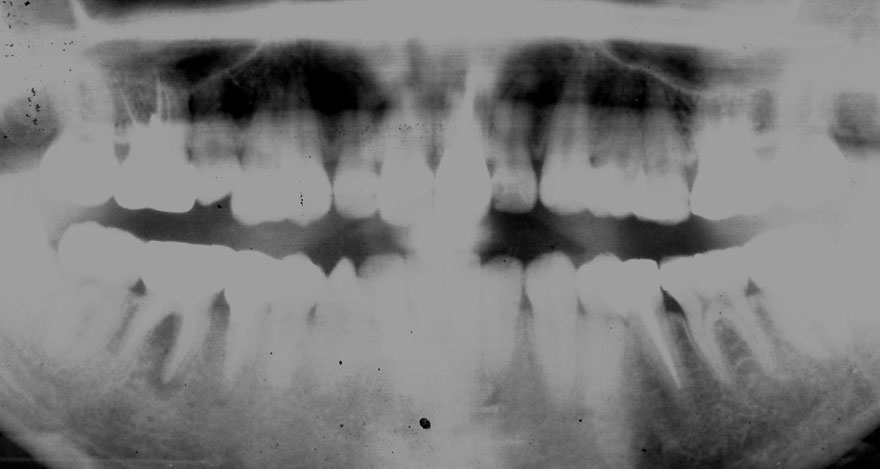

初診時 25歳 男性 平均歯槽骨喪失量:1.43mm

河田歯科医院

30年後 55歳

平均歯槽骨喪失量:1.56mm

22年間喪失量:-0.14mm

年間喪失速度:-0.005mm

(ケア頻度:4.21ヵ月ごと)